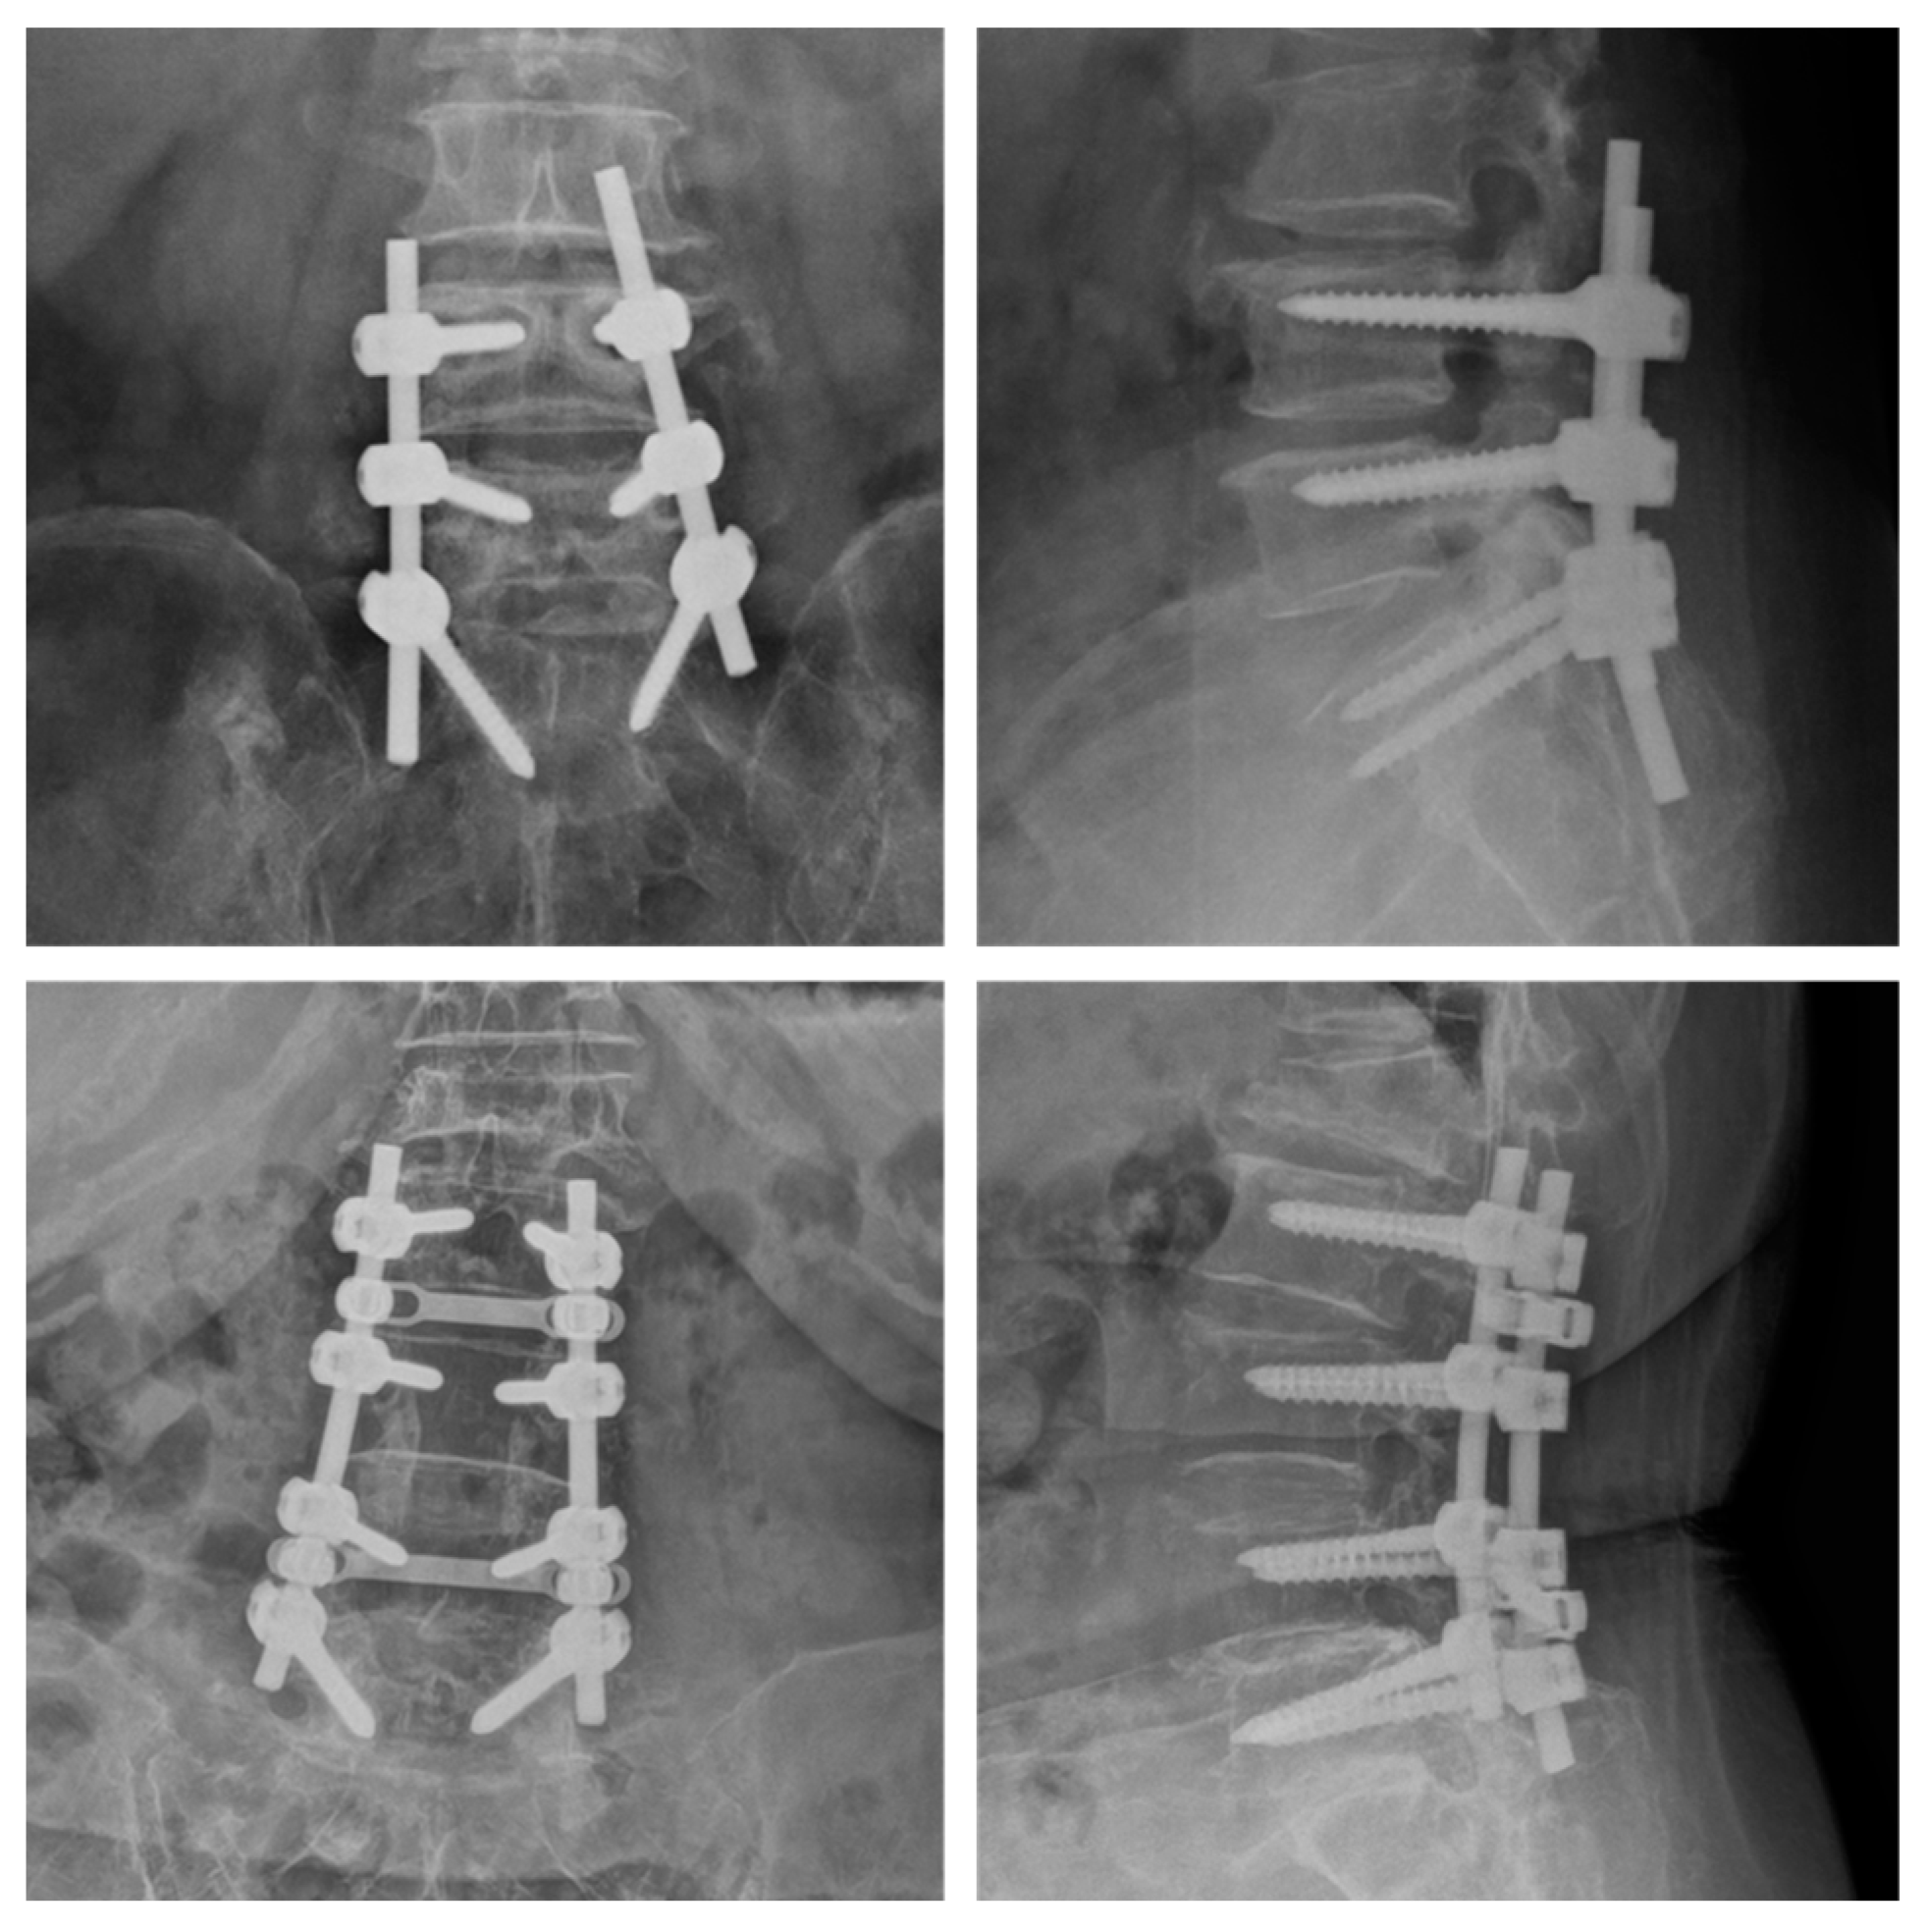

Treatments for spondylolisthesis include selective nerve blocks, which are aimed at reducing back pain, and posterior spinal fusion treatments that help stabilize the spinal structure, as shown in Figure 12.

Figure 12.

Posterior spinal fusion.